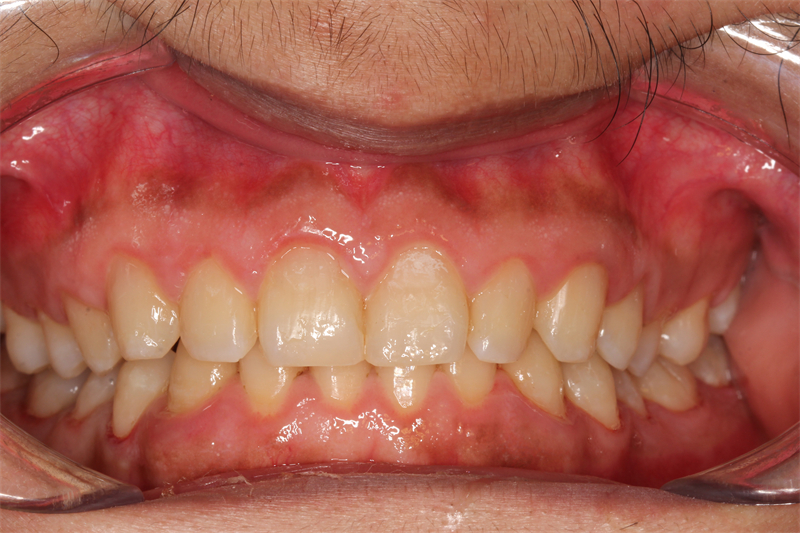

經過幾周的治療,小程終于看到了自己牙齒的顯著變化。他的牙齒變得更加潔白、有光澤,而且再也沒有了之前的酸軟和異味問題。當他再次站在鏡子前微笑時,他看到了自己久違的自信和笑容。這一刻,他深深地感激柳州市人民醫院口腔科的醫生和護士們,是他們用專業的技術和認真負責的態度幫助他重拾了自信和微笑。